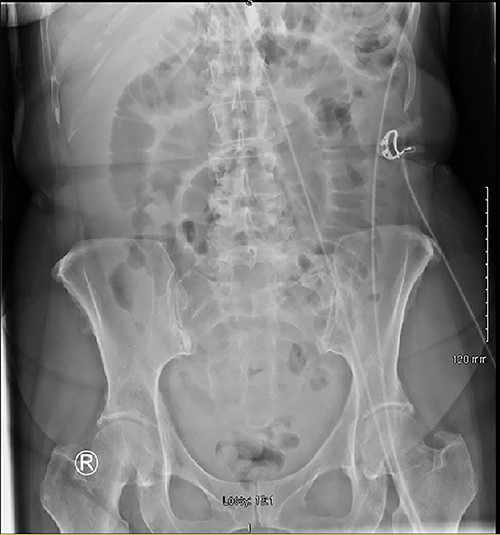

A 60 year-old female patient presented to the emergency department complaining of worsening central abdominal pain for last 4 days, associated with nausea and bilious vomiting, an episode of loose bowel motion and ‘general unwell feeling’ for last 5 weeks. She also presented 5 weeks ago with vague abdominal pain, which improved with Buscopan® and Solpadeine®; blood results were normal, so she was discharged home. She had a vague central abdominal tenderness on examination, a C-Reactive Protein (CRP) of 139, and the initial plain film abdomen showed dilated small bowel loops with paucity of air in the large bowel (Fig. 1).